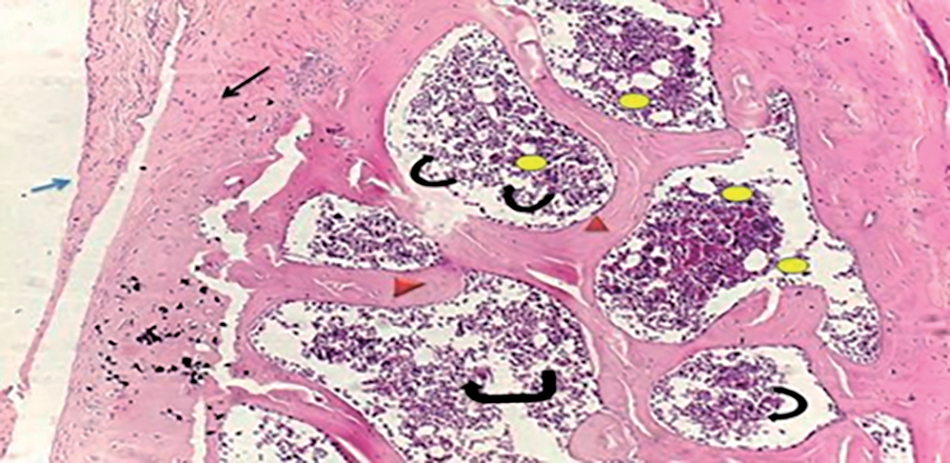

Sections from OA rats at tibia plateau region showed more fibrillation, shrunken chondrocytes with fragmented pyknotic nuclei, and extensive area of degenerated cartilage involving the entire zone of articular cartilage; the fibrillation and fissuring were noticed, and changes like denudation, erosion, and replacement by fibrous tissue were observed (Fig. 12). Moreover, the OA sections from patello femoral joint post 28 days showed underlying bone, increased of osteoclasts and osteoblast activity, alterations in the formation of bone and subchondral structure. This layer appeared with multinucleate cells and embedded within bone matrix, irregular collapse trabeculae, irregular osteoblasts, bone marrow cavity extensively infiltrated with osteoclast, abnormal cellularity, and partial replacement of bone marrow by fibrotic tissue (Figs. 13 and 14).

Fig. 13. Histological section from (OA) rat articular cartilage shows denudation and complete degeneration of cartilage surface (), hyper-proliferation of inflammatory cells (), collapsed subchondral trabeculae () enclosed congested, cellular marrow cavities () and fibrous synovium (). (H & E) stain.

Fig. 14. Section from (OA) rat patello-femoral joint showed collapsed, fissuring trabeculae (), multi-nucleated subchondral bone (), fibrillation and degenerated articular cartilage surface (), fibrous synovium (), hyperproliferation of osteoblast () and more congested marrow cavities () with increased osteoclasts (). (H & E) stain.